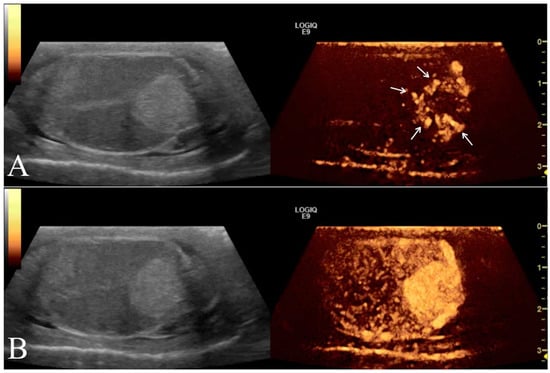

The testicular artery was first detected in the pampiniform plexus by scanning the cranial pole of the testis. Then, the linear probe was moved towards the ventral region of testis to locate the marginal artery. Finally, the ultrasound beam was oriented to optimize the visualization of any lesions present and characterize their blood flow. Based on color Doppler imaging, the blood flow of the lesion was classified as either absent or present and, in such a case, as peripheral or intralesional (Figure 2A). Using pulsed wave mode, a sample volume was successively placed on the pampiniform plexus as well as marginal and lesion arteries (if present) to record the waveforms of at least three consecutive cardiac cycles. The PW was set as follows: frequency 3.1 MHz, pulse repetition frequency 3.3 kHz, and Gain 41 dB. The sample volume, the region where the vessel was studied, was positioned in the artery that allowed the best insonation angle when both peri and intralesional vessels were detected simultaneously in the same lesion. The insonation angle between the Doppler stream and the course of the vascular segment was manually aligned and the measured blood flow velocity was automatically corrected. The measurements with an angle >20° were disregarded. However, the measurements of three different waveforms in each vessel were taken and we made an average to reduce any errors. For each testicular artery, quantitative blood flow analysis included the evaluation of peak systolic velocity (PSV), end diastolic velocity (EDV), resistance index (RI), and pulsatility index (PI) (Figure 2B).

Figure 2. Representative Doppler characterization of a nodular lesion (leydigoma) found in the left testicle of a 11 year old Italian Mastiff. In particular, picture 2 (A), recorded by color Doppler, allowed the visualization of blood flow distributed peripherally to the lesion, while picture 2 (B) showed the same blood flow sampled by pulsed wave mode for quantitative analysis.